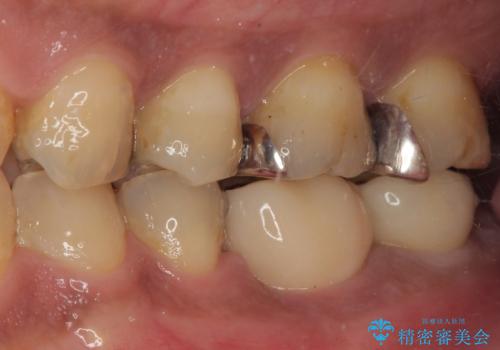

治療は順調に進み、わずか3ヶ月でセラミッククラウンを装着することができました。

他の歯への影響もなく、無事に治療を終えることができました。